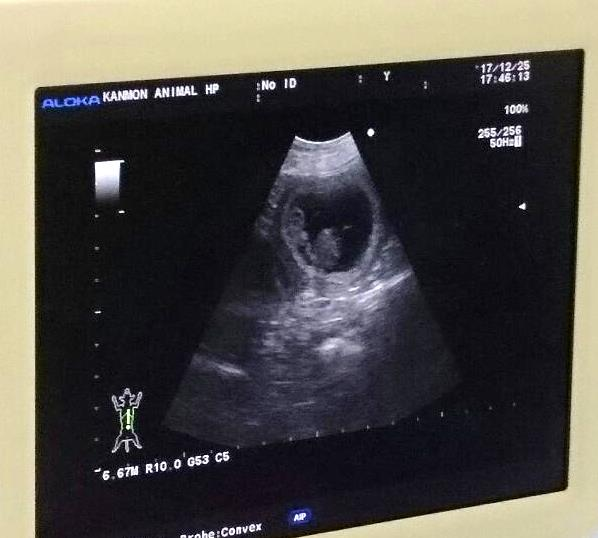

エコー検査

胎児が確認できました♪

妊娠鑑定:2017年12月25日